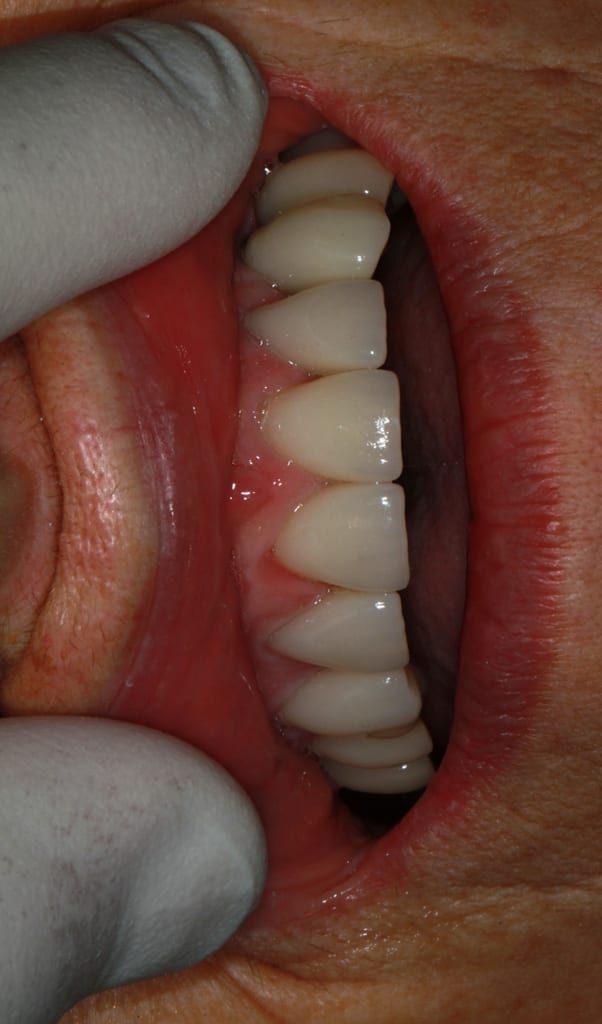

des nouvelles de ce cas... mise en charge des implants et attelle incisive mandibulaires avec suppression du diastème

expansion qui donne un résultat correcte je crois